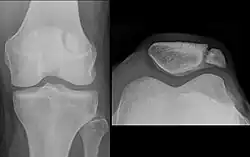

The upper three-quarters of the patella articulates with the femur and is subdivided into a medial and a lateral facet by a vertical ledge which varies in shape.

In the adult the articular surface is about 12 cm2 (1.9 sq in) and covered by cartilage, which can reach a maximal thickness of 6 mm (0.24 in) in the centre at about 30 years of age. Owing to the great stress on the patellofemoral joint during resisted knee flexion, the articular cartilage of the patella is among the thickest in the human body.

The upper three-quarters of the patella articulates with the femur and is subdivided into a medial and a lateral facet by a vertical ledge which varies in shape. Four main types of articular surface can be distinguished:

- Most commonly the medial articular surface is smaller than the lateral.

- Sometimes both articular surfaces are virtually equal in size.

- Occasionally, the medial surface is hypoplastic or

- the central ledge is only indicated.